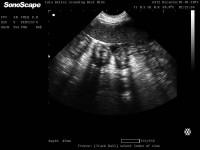

This week I cover a topic that it is fair to say has shaped the last few years of my life – namely, equine pregnancy. It is particularly topical given the launch of the new iScan which is perfect for advanced equine pregnancy work. Although previous articles have touched on this subject where I discussed my PhD in general, here I will discuss particular landmarks you should look out for during early equine pregnancy (day 120 of gestation).